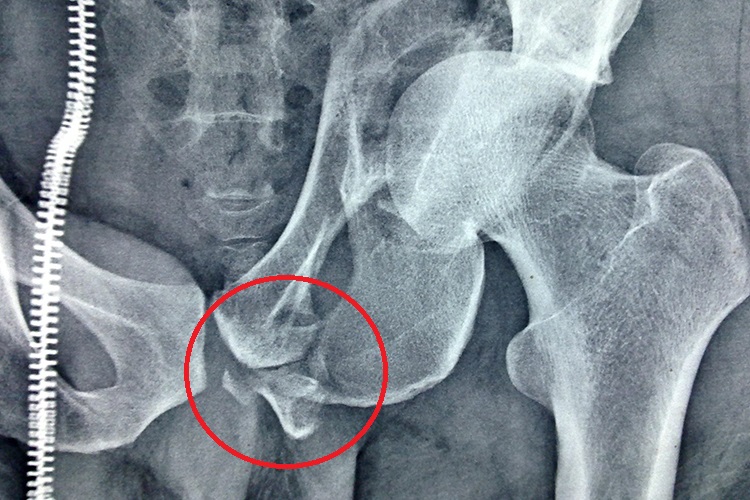

左侧耻骨骨折是指在骨盆骨折中创伤累及或髋臼骨折延伸至左侧耻骨,耻骨弓骨性结构完整性破坏,皮质连续性中断,骨折碎片移位。

耻骨骨折后,患者可感到腹下胀痛,耻骨联合处有明显压痛,坐和卧均感疼痛。轻者能站立,但旋转脊柱时疼痛;重者不能站立,髋关节后伸和外展均有明显疼痛;用手触摸时疼痛加剧,而且有明显骨擦音。X线检查可看到明确的骨折线。